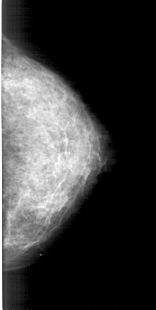

A_1459_1.RIGHT_MLO

RIGHT_MLO LINES 5491 PIXELS_PER_LINE 2626 BITS_PER_PIXEL 12 RESOLUTION 43.5 NON_OVERLAY